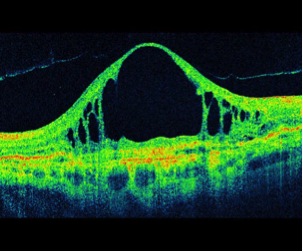

El OCT macular (tomografía de coherencia óptica) es una técnica muy moderna y no invasiva de imagen que permite el diagnóstico, control y seguimiento de los problemas de mácula, como la degeneración macular, el edema macular diabético y de la trombosis, el agujero macular y las membranas epi maculares entre otros.

Examen OCT de Edema macular

Examen OCT de: Agujero macular Membrana Epi Macular

Examen OCT de degeneración macular etarea exudativa